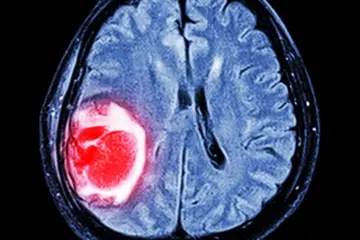

ضرورت حمایت از تحقیقات ملی درباره داروی یک سرطان بدخیم مغزی

یک متخصص فارماکولوژی بالینی گفت: گلیوبلاستوم مولتی فرم، یکی از بدخیم‌ترین انواع تومورهای مغزی است که این بیماری تا حد زیادی غیرقابل درمان کامل و قطعی است.